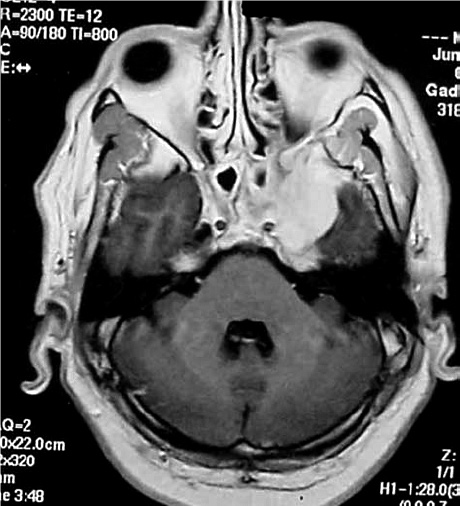

El patógeno asociado a la aspergilosis diseminada es el Aspergillus fumigatus. Clínicamente, la infección primaria a menudo comienza en las vías respiratorias o los senos paranasales; y por diseminación hematógena puede llegar a infectar al SNC. En la RM los aspergilomas se ven isointensos en T1, extremadamente hipointensos en T2 y captan dando un brillo homogéneo e intenso (20). Las imágenes potenciadas en difusión muestran restricción de la difusión debido a pus intracavitaria o a infarto por invasión intravascular. Las características imagenológicas son definidas como lesiones con realce en anillo en núcleos basales, tálamo y cuerpo calloso. En la neuroespectroscopía se evidencia aumento del índice colina-creatinina, disminución de N-acetil-L-aspartato (NAA) y pico de lactato (20). El diagnóstico definitivo es, por lo general, histopatológico (21).

La figura 2 corresponde a una imagen axial por RM en T1-W, que muestra masa en parte medial adyacente al polo temporal izquierdo con extensión al seno paranasal adyacente de un aspergiloma.

Tomado de Siddiqui et al. (14).